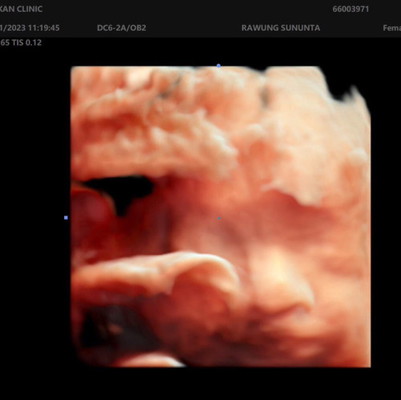

ขออนุญาตสอบถามค่ะ แบบนี้ปากแหว่งหรือป่าวคะ

แบบนี้น้องปากแหว่งหรือป่าวคะ ตอนอัลตราซาวด์น้องนอนคว่ำเลยเห็นไม่ชัด คุณหมอก็ไม่ได้พูดอะไร พอมาดูภาพตอนนี้แม่กังวลมากเลยค่ะ 😢

ถ้าหมอไม่ได้พูดอาไรก้อปกติคะ